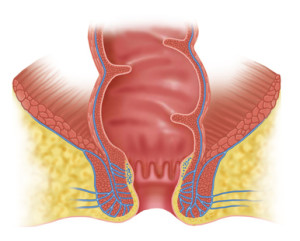

Проктологические заболевания довольно распространены, статистика указывает, что более 70% населения страдают от заболеваний кишечника и прямой кишки. Среди заболеваний прямой кишки в троицу лидеров входит трещина заднего прохода. Так что такое трещина заднего прохода? Трещина заднего прохода – это проктологическое заболевание, характеризуется изменением состояния тканей прямой кишки и анального прохода, доставляет множество неудобств, является причиной психологического и физического неудобства. Возникает заболевание у людей разного возраста, даже у детей. Патология развивается под воздействием предрасполагающих факторов, которые можно избежать. Заболевание «трещина анального прохода» не стоит игнорировать или лечить народными методами. При неправильном лечении возникают условия для воспаления, ухудшения общего состояния или развития хронической трещины заднего прохода. Лучше обратится в клинику на начальной стадии, провести консервативное лечение и восстановить состояние тканей, функцию органа.

Трещины анального отверстия возникают редко самостоятельно в результате травмы заднего прохода, чаще всего это следствие длительного нарушения пищеварительной системы, такой как хронические запоры, диарея или течение геморроя. Часто заболевание возникает у женщин в период вынашивания ребёнка, после тяжёлых родов.

Анальные трещины без рубцевания лечатся консервативными методами, хронические трещины заднего прохода требуют более тщательного подход к терапии и проведения хирургического лечения. Симптомы анальной трещины схожи с другими проктологическими заболеваниями, например похожи на симптомы таких заболеваний как геморрой, заболевания толстого кишечника, парапроктит и т.д. Поэтому лечение проводится только после уточнения диагноза, определения причин патологического процесса, а значит после качественного обследования и проведения ряда исследований. Если трещины заднего прохода, выявленные на начальной стадии (течение заболевания не более 1 месяца), то проводиться только консервативная терапия. Зависимо от причины анальной трещины проводится подбор методов улучшения состояния. Нарушение стула устраняется коррекцией питания, медикаментозными средствами, лечебной гимнастикой и некоторыми физиотерапевтическими методами. Многим пациентам помогает улучшить состояние гидроколонотерапия и клизмы.